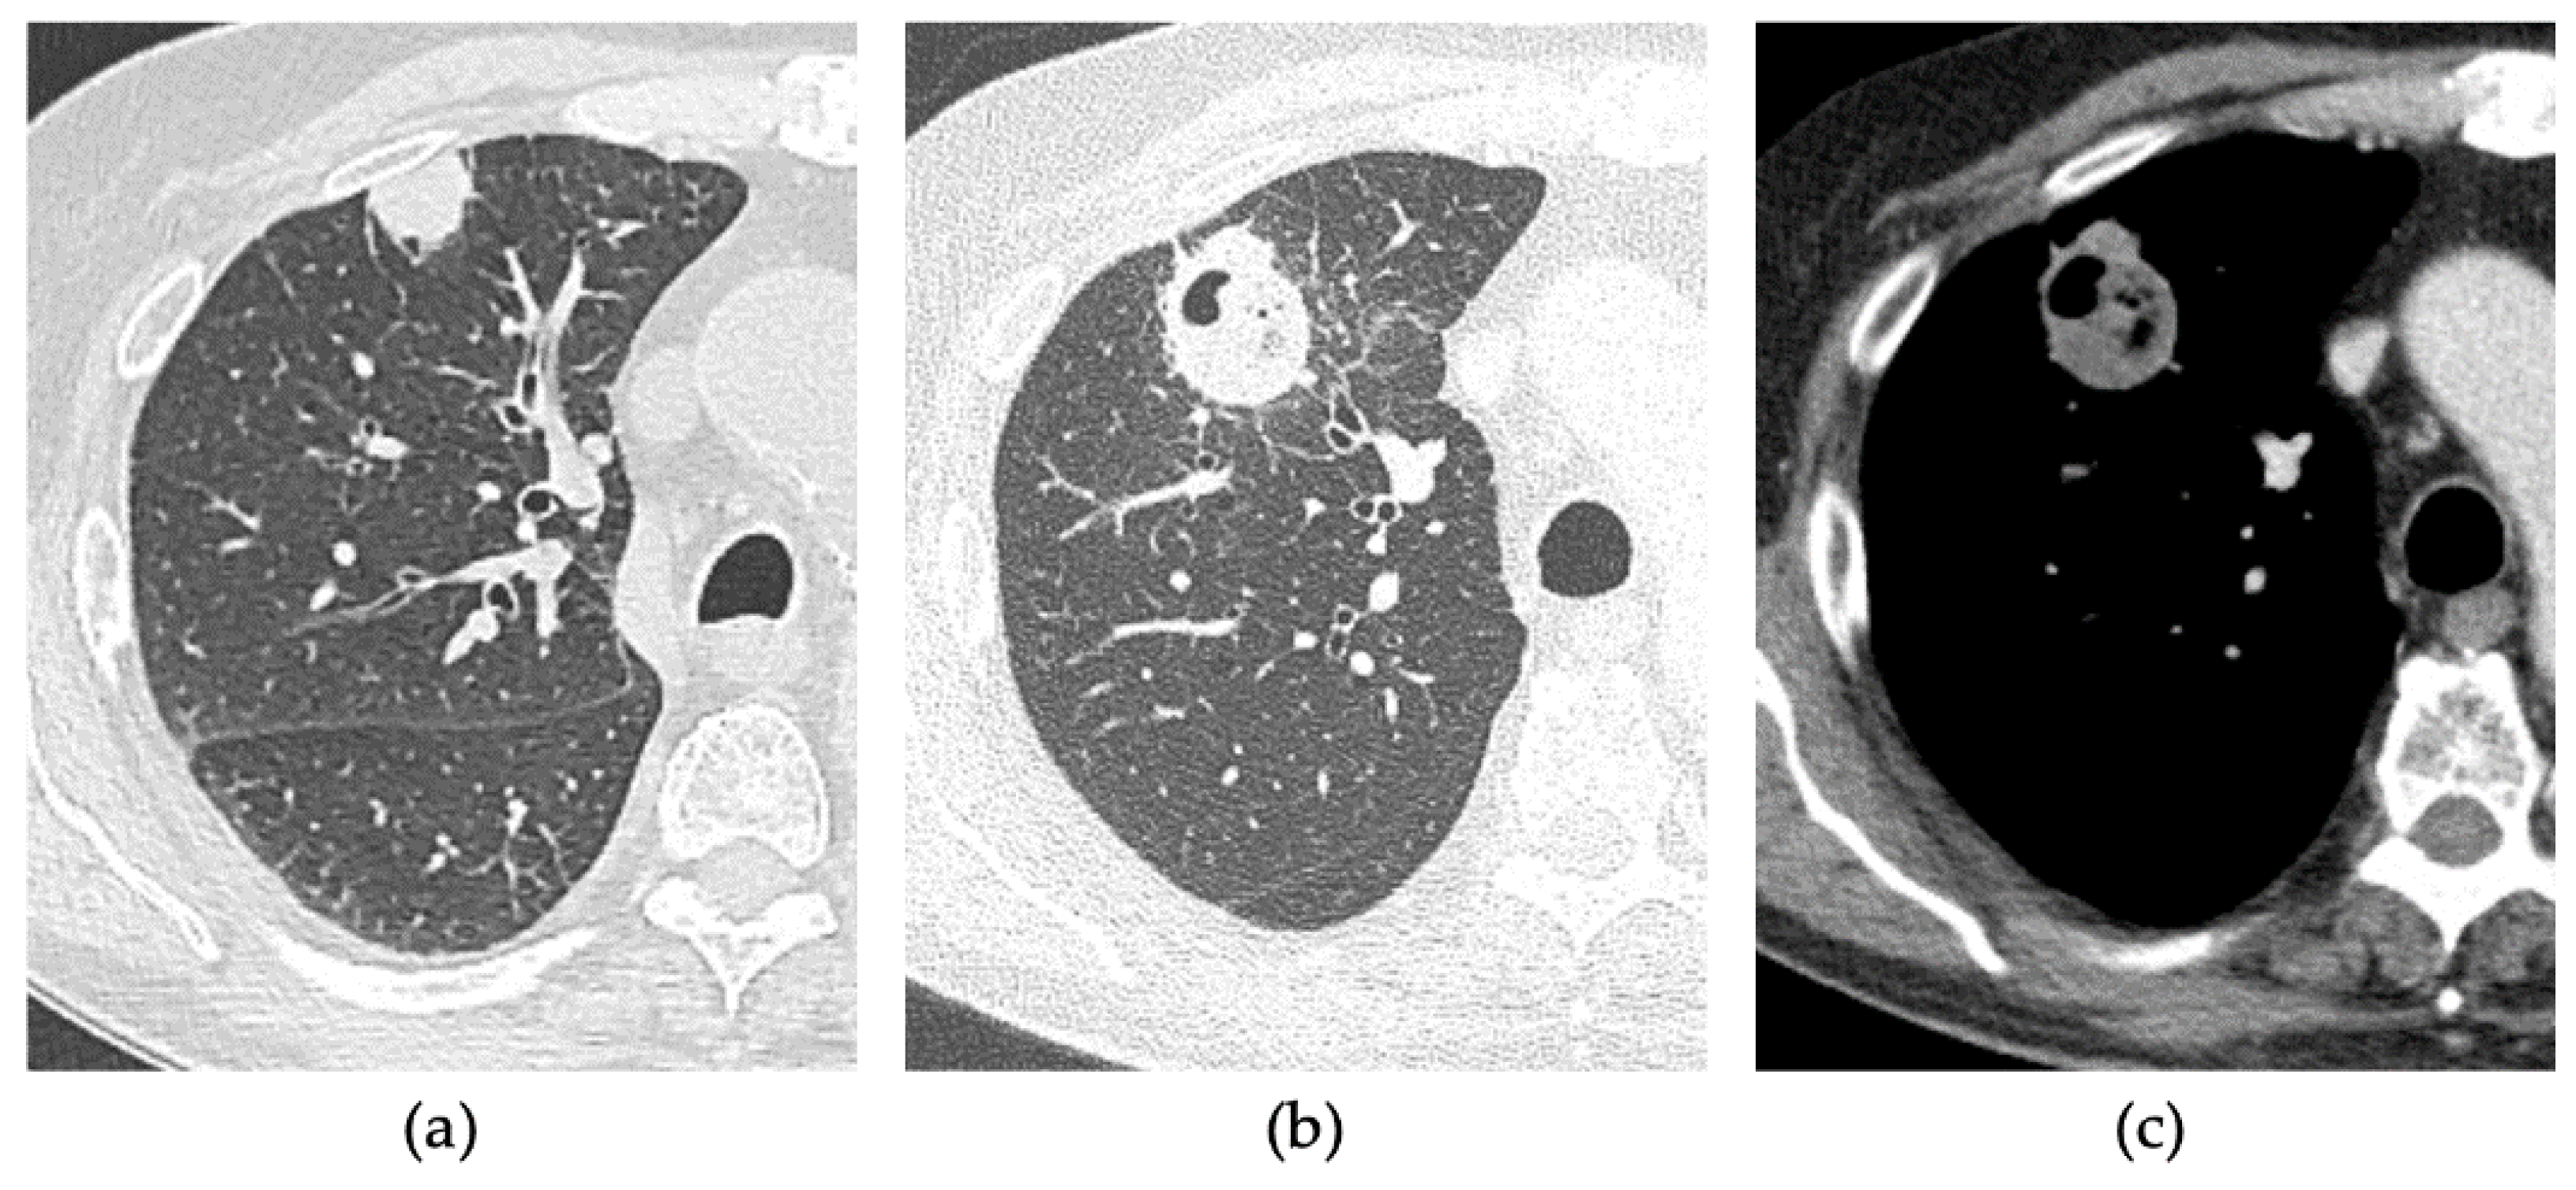

2.2. Procedure

2.3. CT Follow-Up